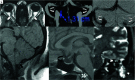

Background and purpose: Dural venous sinus stenosis has been associated with idiopathic intracranial hypertension and isolated venous pulsatile tinnitus. However, the utility of characterizing stenosis as intrinsic or extrinsic remains indeterminate. The aim of this retrospective study was to review preprocedural imaging of patients with symptomatic idiopathic intracranial hypertension and pulsatile tinnitus, classify the stenosis, and assess a trend between stenosis type and clinical presentation while reviewing the frequencies of other frequently seen imaging findings in these conditions.

Materials and methods: MRVs of 115 patients with idiopathic intracranial hypertension and 43 patients with pulsatile tinnitus before venous sinus stent placement were reviewed. Parameters recorded included the following: intrinsic or extrinsic stenosis, prominent emissary veins, optic nerve tortuosity, cephalocele, sella appearance, poststenotic fusiform enlargement versus saccular venous aneurysm, and internal jugular bulb diverticula. χ2 cross-tabulation statistics were calculated and recorded for all data.

Results: Most patients with idiopathic intracranial hypertension (75 of 115 sinuses, 65%) had extrinsic stenosis, and most patients with pulsatile tinnitus (37 of 45 sinuses, 82%) had intrinsic stenosis. Marked optic nerve tortuosity was more common in idiopathic intracranial hypertension. Cephaloceles were rare in both cohorts, with an increased trend toward the presence in idiopathic intracranial hypertension. Empty sellas were more common in idiopathic intracranial hypertension. Cerebellar tonsils were similarly located at the foramen magnum level in both cohorts. Saccular venous aneurysms were more common in pulsatile tinnitus. Internal jugular bulb diverticula were similarly common in both cohorts.

Conclusions: In this cohort, most patients with idiopathic intracranial hypertension had extrinsic stenosis, and most patients with pulsatile tinnitus had intrinsic stenosis. Awareness and reporting of these subtypes may reduce the underrecognition of potential contributory stenoses in a given patient's idiopathic intracranial hypertension or pulsatile tinnitus.